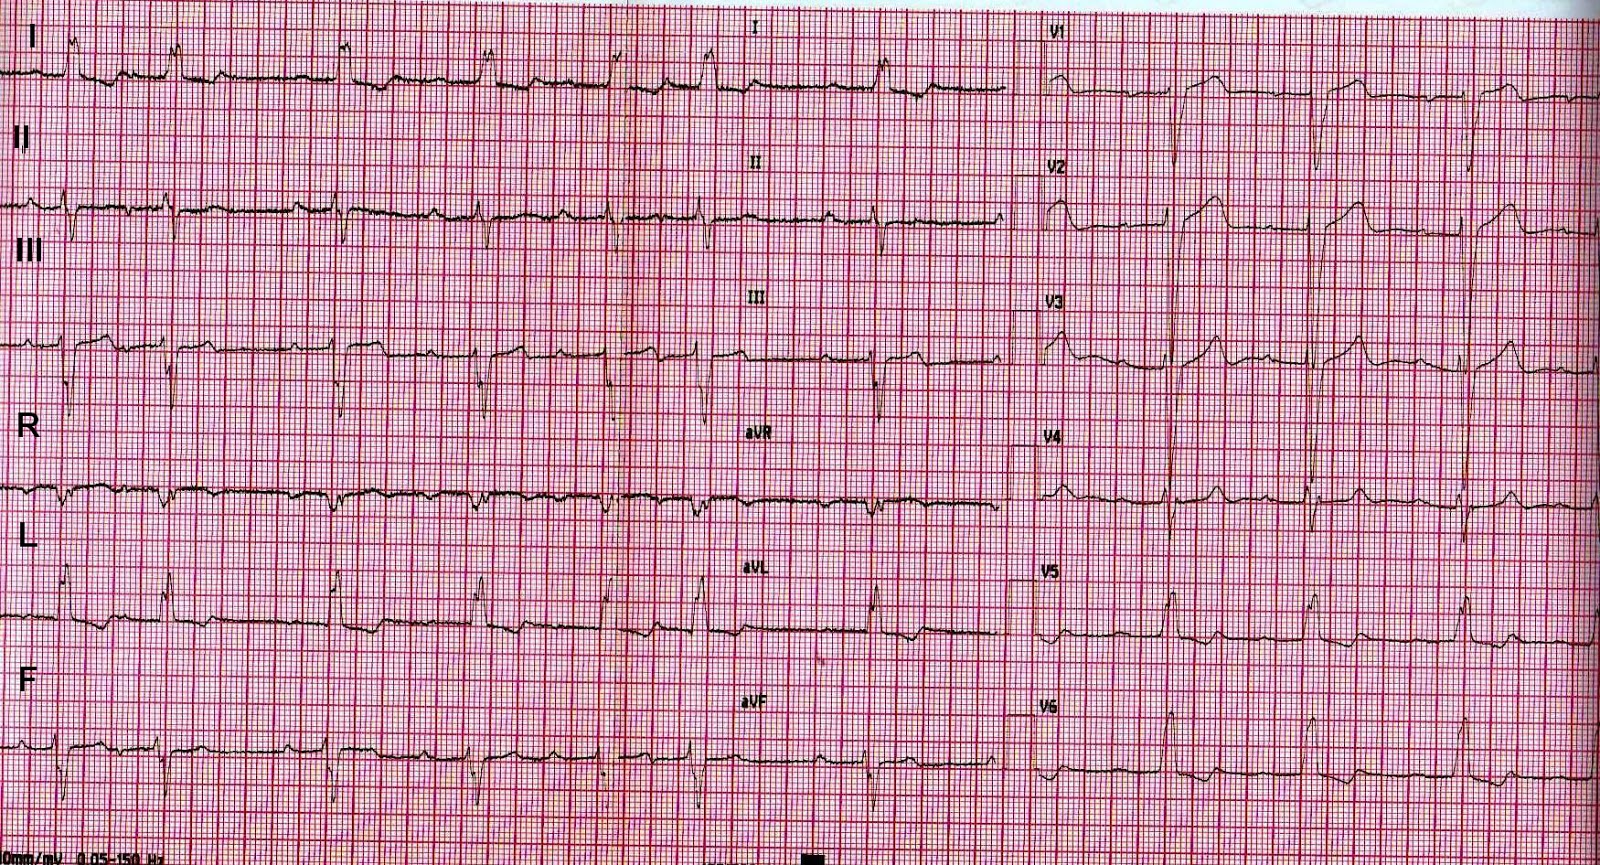

Which are the abnormal findings in this ECG ?

What are the findings in this ECG ?

Rhythm : sinus. PR interval prolonged (first degree atrioventricular block).

Some supraventricular premature beats. Left bundle branch block (LBBB). Frontal QRS axis with left deviation.

Frontal QRS axis is at about -30 degrees, since the net QRS is almost isoelectric in lead II. This fact alone indicates that the axis can be either -30 degrees, or +150 degrees, but the QRS is positive in lead avL, so the axis cannot be + 150 degrees. It is at -30 degrees. Also note that lead avL has the larger positive algebric sum of the QRS waves.